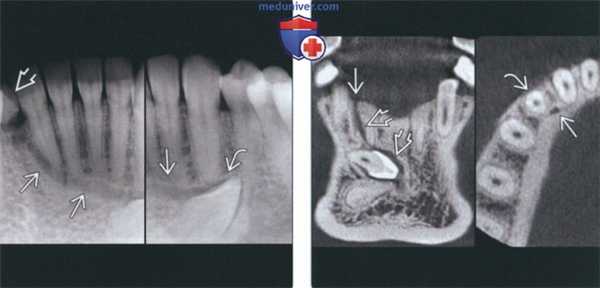

(Слева) На периапикальных рентгенограммах визуализируются четко очерченный рентгенонегативный тракт проводника зу6а (ПЗ) связанный с верхним краем коронки постоянного клыка нижней челюсти справа, мигрировавшего на противоположную сторону. Тракт доходит до альвеолярного гребня возле оставшегося временного клыка справа.

(Справа) На корональной (справа) и аксиальной (слева) КЛКТ визуализируется ПЗ, идущий от коронки импактного постоянного клыка нижней челюсти справа до альвеолярного гребня с язычной стороны от сохранного временного клыка.